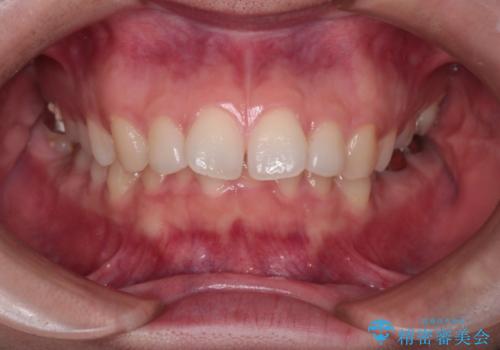

【インビザライン】前歯を引っ込めたい

- 前歯が出ていることを主訴に来院された患者様です。

抜歯を希望されなかっため、臼歯部の遠心移動やIPRを行い配列を行っています。

抜歯をしていない矯正となるため、口元に大きな変化は認められません。